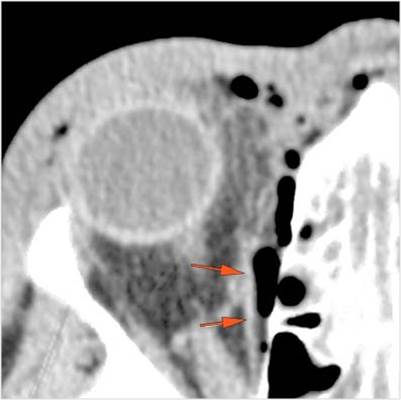

The circumferential extraconal and the intraconal orbital fat are edematous. |

Yes | NA |

The extraocular muscles are swollen. |

Proptosis is present. |

There is evident general optic sheath swelling or swelling at the junction of the globe and sheath to suggest an optic sheath hematoma. |

LeFort type III, orbital zygomatic and orbital floor and fronto - naso-ethmoidal complex fractures with possible injury optic nerve/sheath - extent described above.

Possible optic sheath hematoma - suggest the option of further consultation by the ophthalmology service.